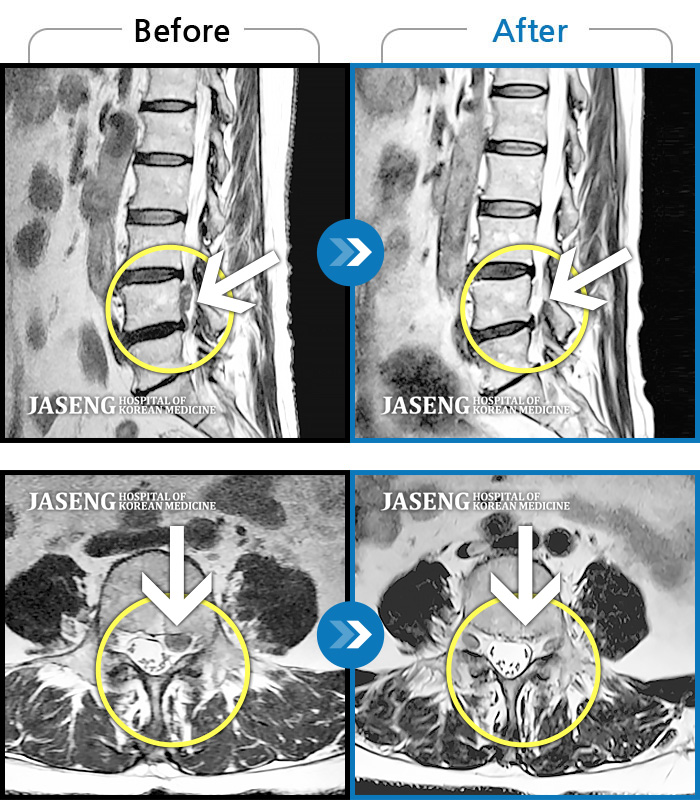

MRI 치료사례

내원시 하부 요추 통증으로 보행 불가하고 야간통증